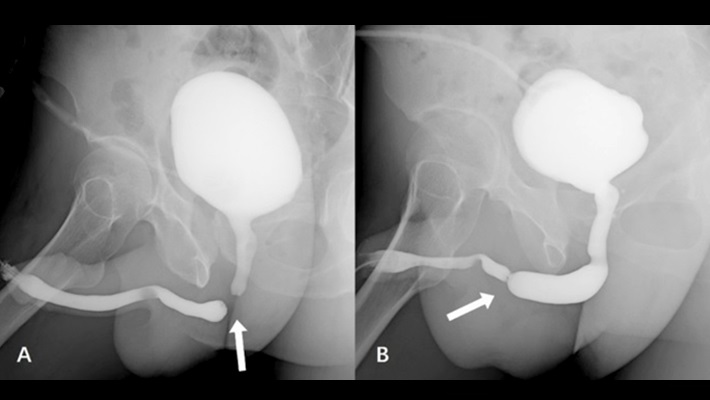

- восходящая (ретроградная) — контрастный препарат вводится через наружное отверстие уретры, что позволяет подробно изучить передний отдел канала;

- нисходящая (микционная) — выполняется во время мочеиспускания, контраст поступает в пузырь либо внутривенно (чаще в составе комбинированного исследования), либо через катетер; метод используется для оценки задней уретры и шейки мочевого пузыря;

- комбинированная — сочетает обе методики и применяется для детальной визуализации уретры на всем протяжении, особенно при сложных травмах и перед реконструктивными вмешательствами.

В уретру вводят тонкий катетер или специальный наконечник, через который медленно подают контрастный препарат, после чего выполняют серию рентгеновских снимков в прямой и косых проекциях. При микционной уретрографии мочевой пузырь наполняют контрастом, а съемку проводят непосредственно во время мочеиспускания.